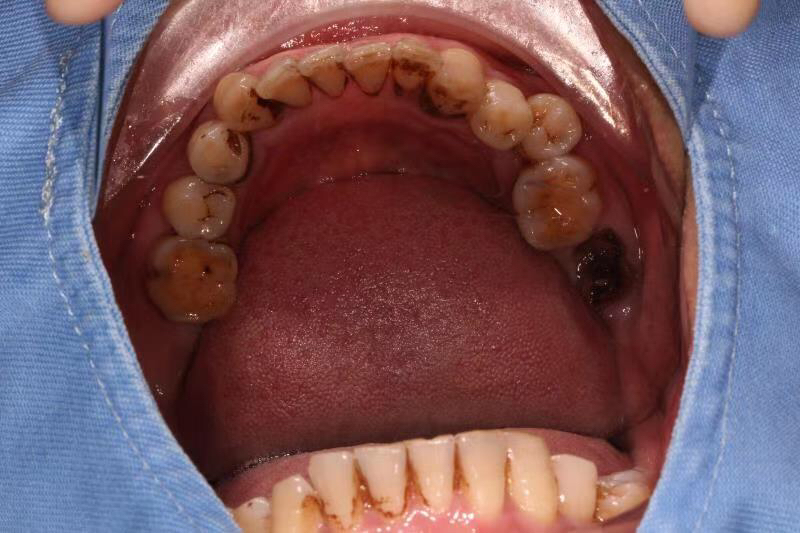

患者中年男性,右下7号牙龋坏未及时处理至残根无法修复,CT检查发现骨量尚可,可以即拔即种,并且不需要植骨,节省了患者治疗周期,整个治疗过程用了4个月患者就戴上了牙齿。